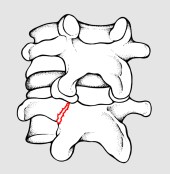

Per spondilolisi si intende l’interruzione di quella parte dell’arco posteriore vertebrale compresa fra le due apofisi articolari (fig 1). Se bilaterale, essa può favorire lo scivolamento in avanti di una vertebra rispetto a quella sottostante, realizzando così la spondilolistesi (fig 2).